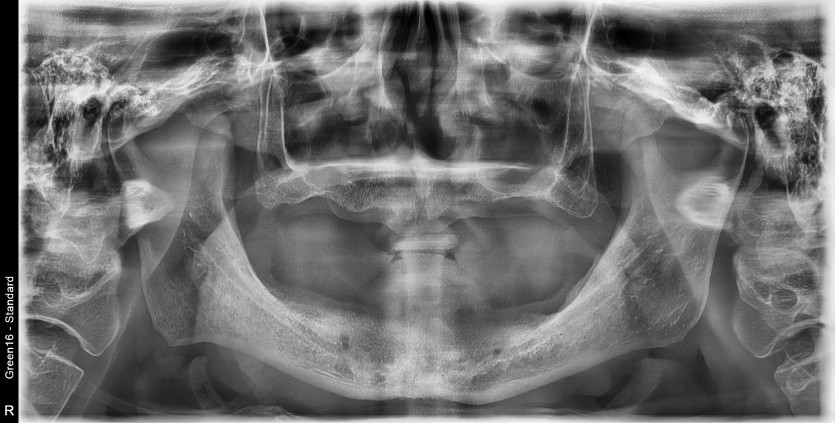

만 61세 전체 임플란트 증례

전체 임플란트 증례입니다.

(하악 풀아치-MUA 진행)

14개의 임플란트로 완성하였습니다.